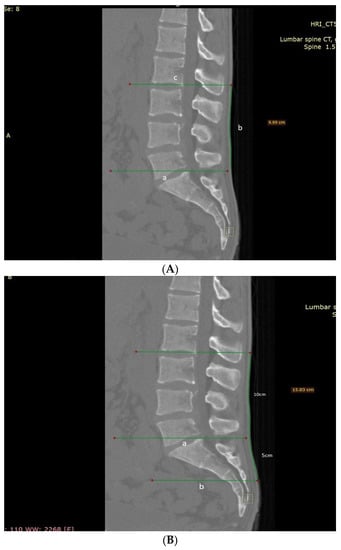

Schober Test and Its Modifications Revisited—What Are We Actually Measuring? Computerized Tomography-Based Analysis